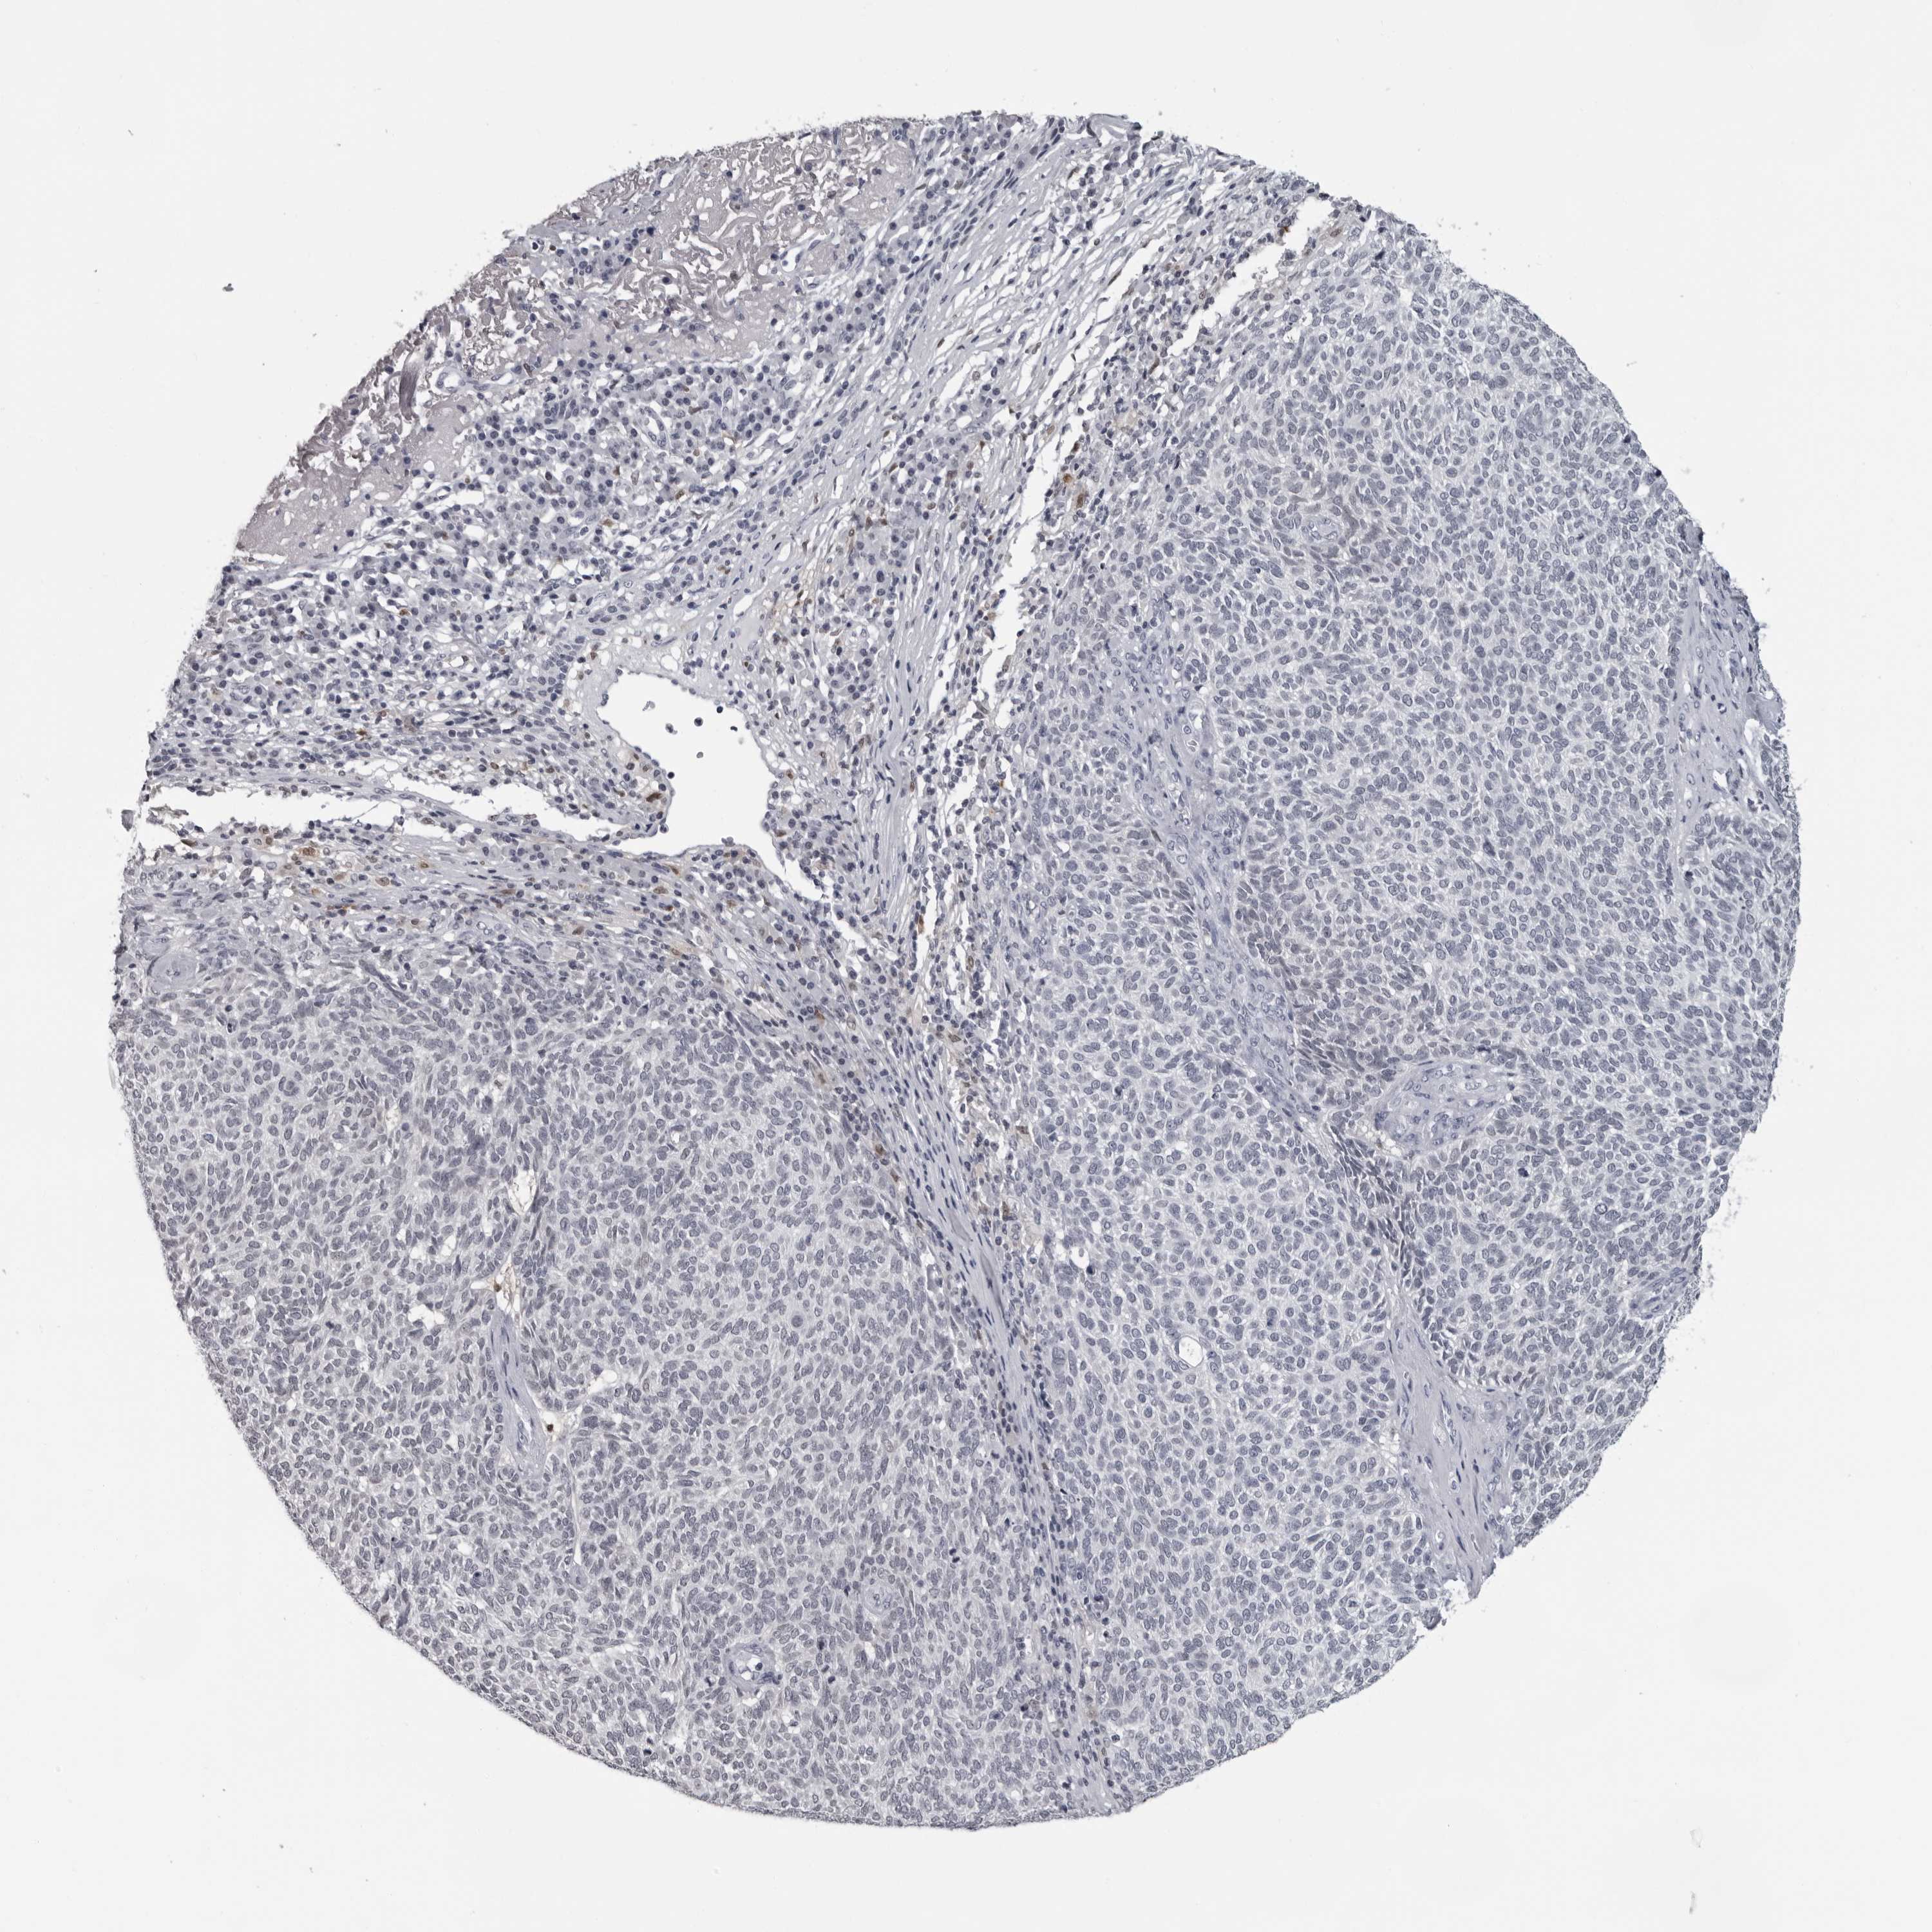

SKIN CANCER - Protein expressioni

A mouse-over function shows sample information and annotation data. Click on an image to view it in a full screen mode. Samples can be filtered based on level of antibody staining by selecting one or several of the following categories: high, medium, low and not detected. The assay and annotation is described here.

Each image is clickable and will lead to virtual microscopy that enables deeper exploration of all samples and also displays staining intensity scores, fraction scores and subcellular localization as well as patient and tissue information for each sample.

Antibody HPA028184

Staining

High

Medium

Low

Not detected

Intensity

Strong

Moderate

Weak

Negative

Quantity

>75%

75%-25%

<25%

None

Location

Nuclear

Cytoplasmic/membranous

Cytoplasmic/membranous,nuclear

Squamous cell carcinoma, NOS

Squamous cell carcinoma, metastatic, NOS